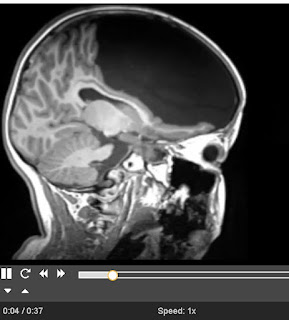

We see below a visual of the girl's brain, from Supplementary Video 11: